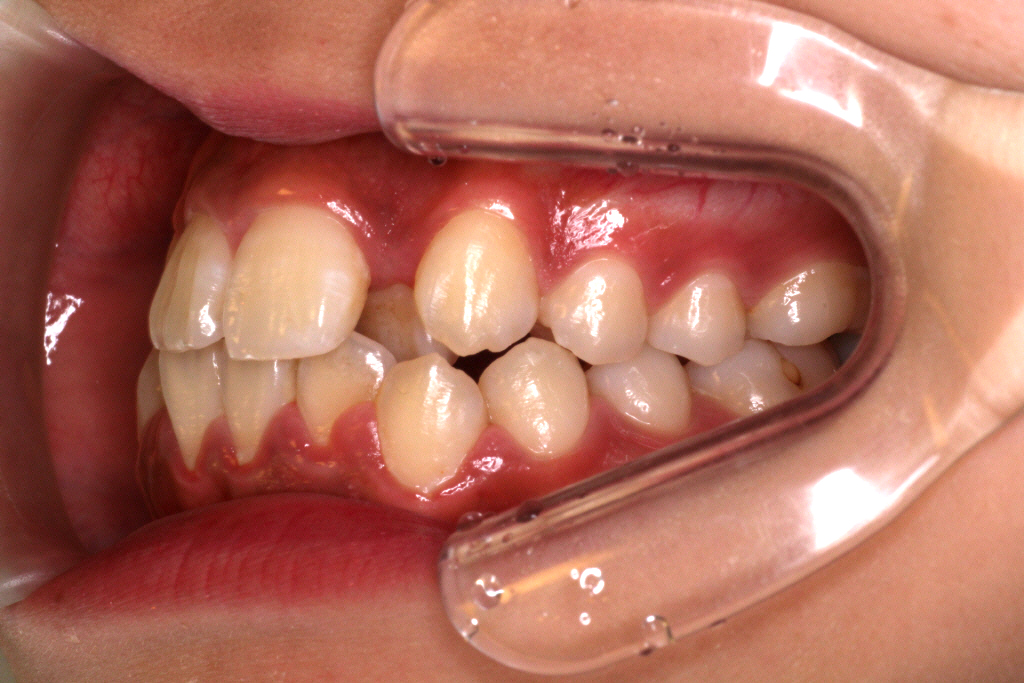

上下マウスピースを37枚最後まで1週間ずつ使い、6ヶ月後のお口の中の状態です。↓

① 左上の2番目の歯が歯列に入っていない

② 右上の2番目の歯が切端咬合と言って上下の歯の先端がぶつかっています。

③ 側方の上下の咬合関係が理想の上1本に対して下2本にはなっていません。

④ 左右の2番目、3番目あたりの噛み合わせがあまく、隙間がある。

このような症状を改善させるために、リファイメント2回目を行いました。